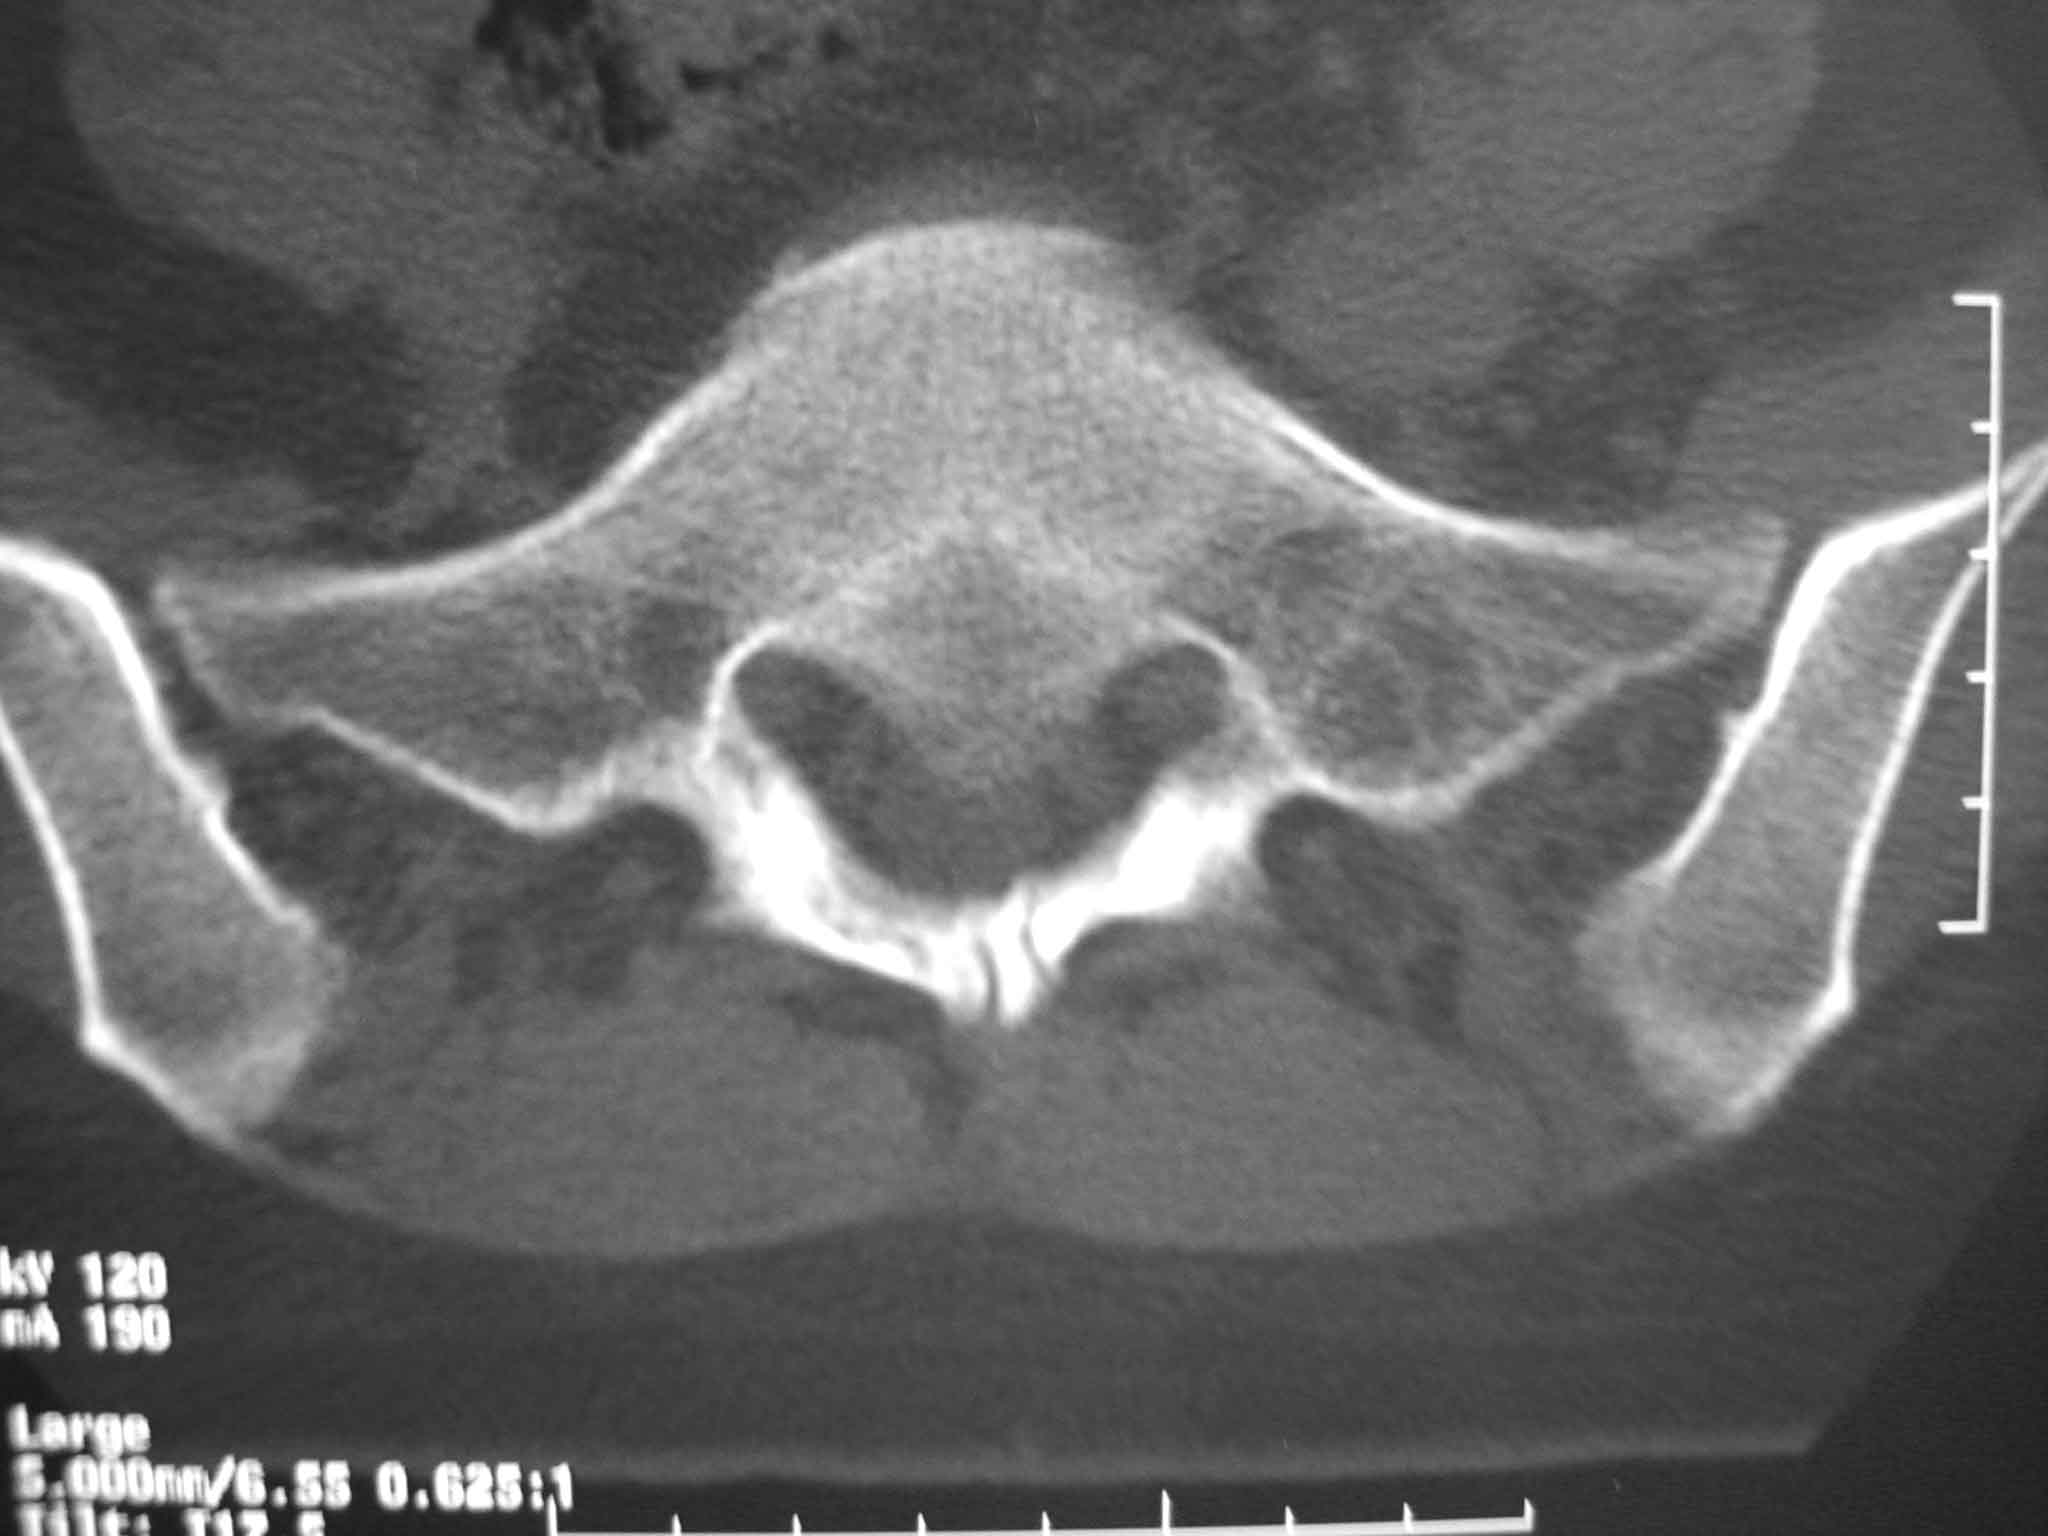

标题: CT15385:F48Y,腰疼一周拍片。

女性,48岁,腰疼一周右腿麻木。不敢弯腰,弯腰疼痛放散至右国窝。

考虑---骶裂---游离棘突

隐性骶椎裂并游离棘突。